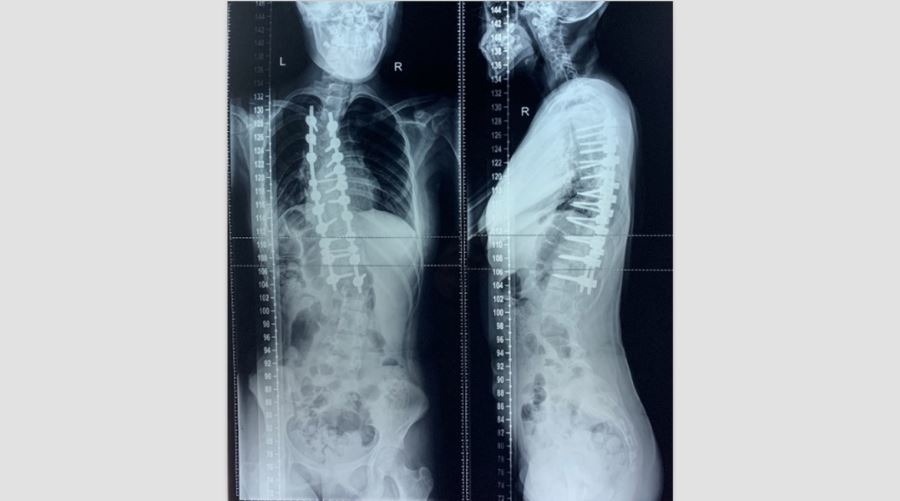

2020年04月彻底根治矫形术胸部Cobb角50°,腰部Cobb角30°站高154cm,坐高122cm